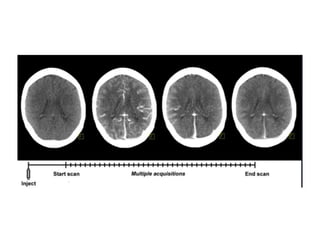

 A typical perfusion CT protocol consists of a baseline acquisition without

contrast enhancement, followed by a dynamic acquisition performed

sequentially after intravenous injection of CM

 The dynamic image acquisition includes a first-pass study, a delayed study, or

both, depending on the pertinent physiologic parameter that needs to be

analyzed.

• Dynamic CT Acquisition  The imaging volume is chosen on

the basis of the unenhanced CT images.

• The first-pass study for perfusion measurements comprises

images acquired in the initial cine/helical phase for a total of

approximately 40 to 60 seconds.